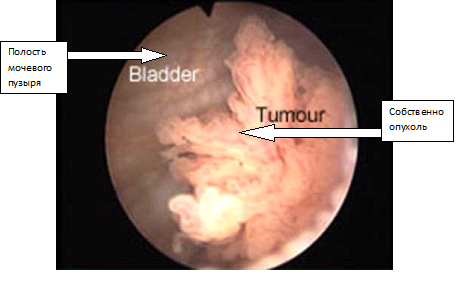

- цистоскопия;

Еще одна достаточно типичная картина рака мочевого пузыря, видимая при цистоскопии: